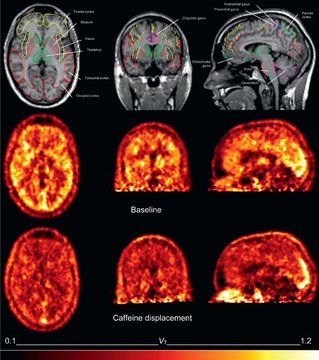

La drogue la plus utilisée, la plus consommée et la moins surveillée au monde.

La caféine.

C'est la raison pour laquelle vous vous sentez fatigué à chaque fois que vous vous réveillez.

Voici pourquoi le café est si dangereux et comment le boire correctement (preuves scientifiques à l'appui) :Image

Image

Au cours des 10 dernières années, j'ai bu 3 à 5 tasses de café par jour.

Il y a 3 mois, j'ai renoncé à la caféine. C'était difficile au début, mais les résultats en valaient la peine.

- Des idées claires

- Plus d'anxiété

- Pas de coup de barre dans l'après-midi

Qu'est-ce qui m'a fait changer d'avis ?

La caféine était de loin la pire des drogues. Image